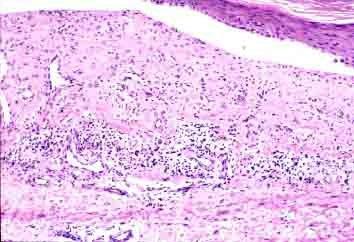

血小板破坏的机制是由于血小板抗体与其相关抗原结合后引起的。当血小板抗体以其Fab片段与血小板相关抗原结合后,抗体分子的Fc片段暴露,并与巨噬细胞的Fc受体结合,导致血小板被吞噬破坏。通过激活补体系统如C3裂解产物C3b附着血小板表面,与巨噬细胞C3b受体结合也导致血小板吞噬。另外,血小板破坏还与巨噬细胞的活性水平有关,所以病毒感染时血小板更易破坏。

3、肝和脾的作用 血小板来源于骨髓巨核细胞,离开骨髓腔后1/3被滞留于脾。脾也是产生血小板抗体的器官,体外培养证实慢性ITP患者脾能产生血小板特异性IgG。患者脾脏组织中的IgG量比正常对照者多5~55倍,约有0.5%~3.5%的ITP脾脏的IgG可与自身血小板或同种血小板相结合。患者脾脏每日平均所产生的抗体良比每日血小板最大结合的需要量高许多倍。目前研究结果认为,抗血小板抗体的合成首先在脾脏,骨髓和其他淋巴组织也有产生;皮质激素能抑制骨髓产生IgG,但不能抑制脾细胞产生IgG。被抗体结合的血小板也主要是在脾破坏,其次是肝,肝破坏受体作用较重的血小板,破坏也较急剧,正常血小板平均寿命为7~11天,患者发病期间血小板寿命明显缩短(约仅1~3天),急性型更短。血小板更新率加速4~9倍。